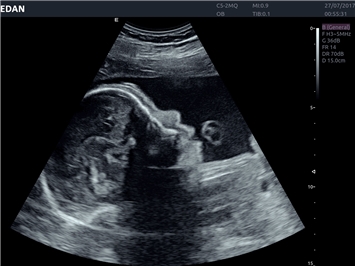

EDAN Acclarix LX4 представляет собой инновационную ультразвуковую систему, построенную на усовершенствованной платформе Acclarix. Сочетание высокого качества визуализации с интеллектуальным рабочим процессом делает эту систему оптимальным выбором для клиник, ценящих эффективность и экономичность.

Система Acclarix LX4 оптимально подходит для:

• Общей визуализации

• Акушерства и гинекологии

• 3D/4D-визуализация с автоматическим редактированием объема (eFace)

• Автоматизированные измерения в акушерстве